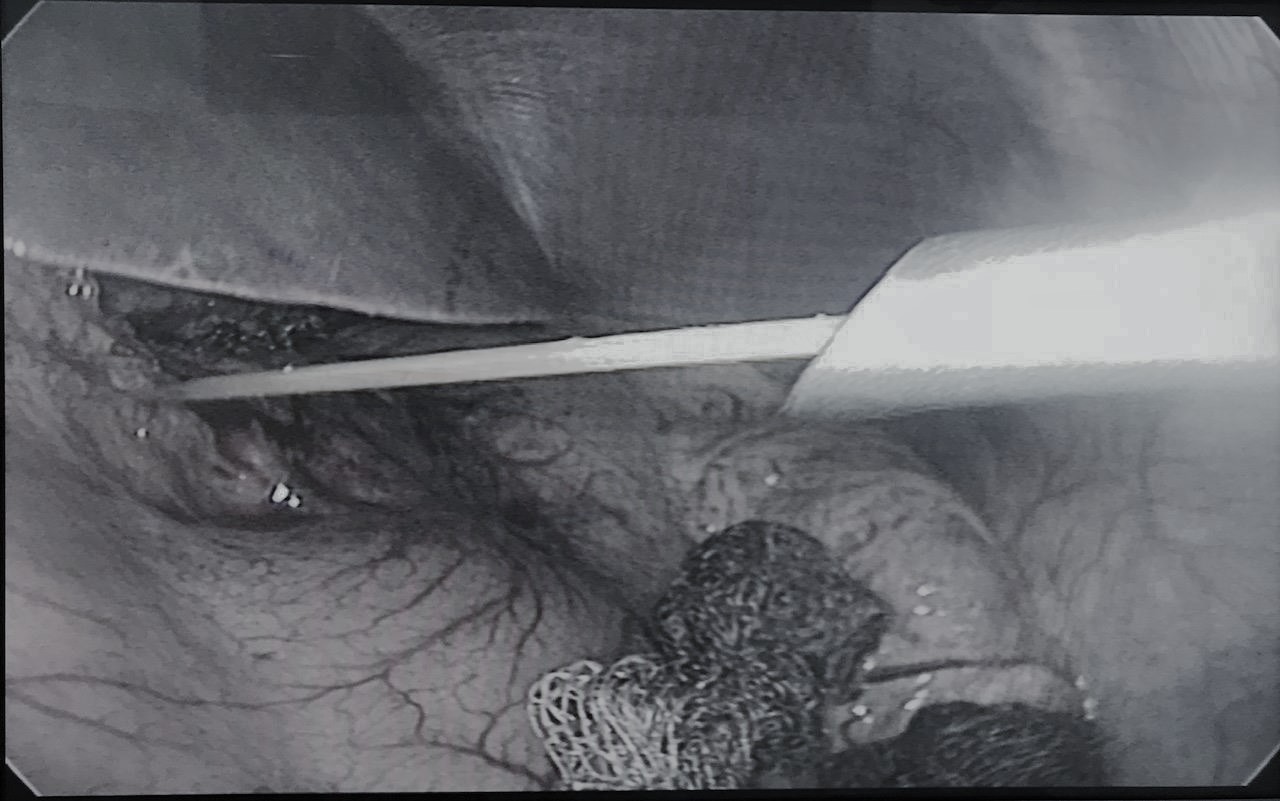

Bệnh viện Trường Đại học Y-Dược Huế hợp tác với Tổ chức IVUmed Hoa Kỳ tổ chức khóa đào tạo liên tục “Cập nhật điều trị ung thư bàng quang”

Trong khuôn khổ hợp tác quốc tế của Bệnh viện Trường Đại học Y-Dược Huế, ngày 6-7/3/2023, Bệnh viện Trường đã tổ chức khóa đào tạo liên tục “Cập...